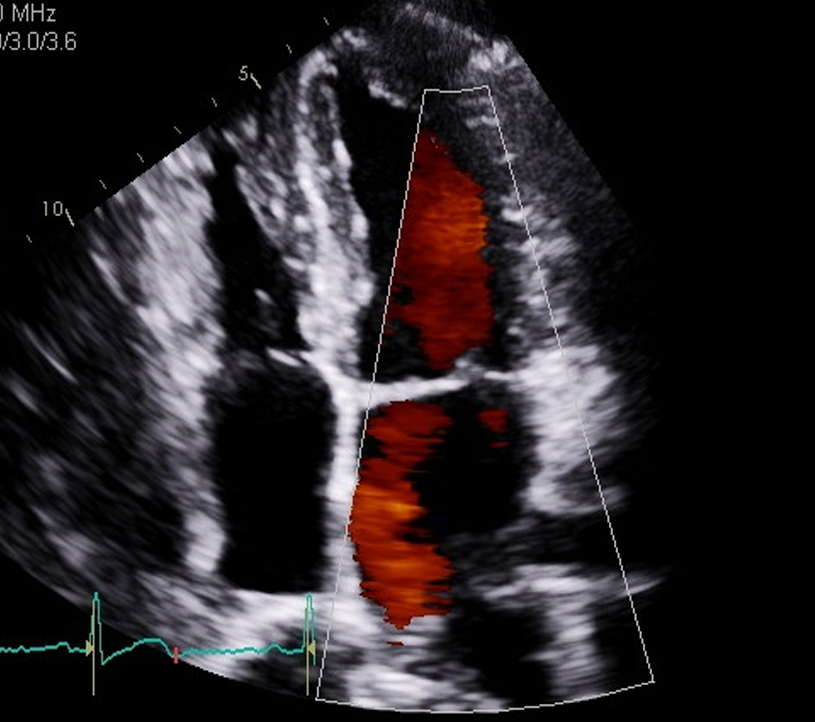

when we do our color flow what are we looing for the step we look at the pulmonary vein with color?

So, we look at the color of the pulmonary veins and for any MR, the normal flow pulmonary vein to LA to MV and the to LV, so any blue flow is going to be that MR reaching back and this red flow will be the pulmonary vein